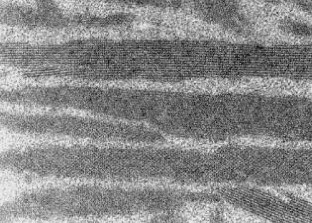

Die Lupusnephritis ist ein bekanntes Phänomen beim systemischen Lupus erythematodes (SLE). Wir untersuchten die Nierenbiopsie einer 30-jährigen Frau mit SLE. Die Anamnese zeigte einen klinisch typischen SLE mit generalisierten Symptomen mit positivem ANA- und Anti-ds-DNA-Titer ohne Nachweis von Lupuskoagulans, des Rheumafaktors, von Kryoglobulinen sowie ohne Antiphospholipid-Antikörper. Eine Paraproteinämie war weder für IgG noch für IgA oder IgM nachzuweisen. Mit Hilfe der Lichtmikroskopie, der Elektronenmikroskopie sowie der Immunelektronenmikroskopie wurden elektronendichte Ablagerungen in subepithelialer, subendothelialer und mesangialer Lokalisation nachgewiesen. Zusätzlich fanden wir sowohl in den elektronendichten Ablagerungen, als auch im angrenzenden Mesangium Kristalle eines elektronendichten Materials. Diese kristallinen Strukturen sind aus IgG und κ-Leichtketten zusammengesetzt, während IgM, IgA sowie λ-Leichtketten mittels Immunelektronenmikroskopie nicht nachzuweisen waren.

Lupus nephritis is a common phenomenon in Systemic Lupus Erythematosus (SLE). We analyzed a renal biopsy of a 30-year-old woman with SLE. The clinical history showed a typical SLE with generalized symptoms without demonstrable lupus coagulant, positive for anti-nuclear antibodies and anti-ds-DNA antibodies but negative for rheumatoid factor, cryoglobulins and antiphospholipid antibodies. A paraproteinemia for IgA, IgG and IgM was not detectable. Using light, electron and immunoelectron microscopy electron-dense deposits were noted in subepithelial, subendothelial and mesangial position. Most remarkably, the electron-dense deposits and mesangial areas in the vicinity of deposits contained an electron-dense crystalline material. The crystalline structures were composed of IgG and kappa light chains, while they were negative for IgM, IgA and lambda light chains, as demonstrated by immunoelectron microscopy.

Abb. 3.